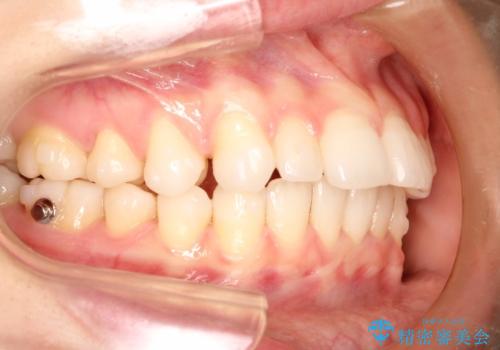

インビザラインで出っ歯を改善する 抜歯をしないinvisalign治療

- 非抜歯・遠心移動による前突の改善をマウスピースにて計画した。

非抜歯矯正の場合、大きく前歯を下げることはできませんが、奥歯の遠心移動や歯のサイズダウンにより歯軸を立て、見かけ上の出っ歯感をある程度改善することができます。